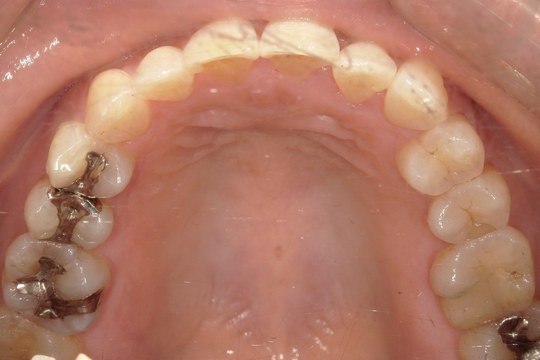

Y.S. 30代男性

全体的にガタガタしているのが気になるという主訴だったため、上下左右第一小臼歯を抜歯し、叢生を並べました。

治療の期間:R3. 9/1〜R5. 10/31

治療の価格:88万円